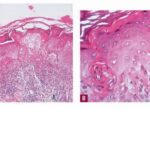

intensity of epidermal necrosis varies from vacuolated individual keratinocytes surrounded by lymphocytes (satellite cell necrosis) at the basal unit to confluent necrosis in association with intraepidermal and subepidermal vesicles. The dermal infiltrate comprises lymphocytes and histiocytes. Eosinophils may also be present. Although one study has noted a significant number of eosinophils in drug-induced EM, this has not been noted by others. In the authors’ estimation, a generous number of eosinophils exclude EM. One study has found that an acrosyringium concentration of apoptotic keratinocytes in EM is a clue to a drug etiology . In early lesions of SJSITEN, apoptotic keratinocytes are observed scattered in the basal layer of the epidermis. In established lesions, there are numerous necrotic keratinocytes, even full-thickness epidermal necrosis, and a subepidermal bulla. The dermal inflammatory infiltrate is sparser in TEN than in EM (Fig. 9-278). Extravasated erythrocytes are commonly found within the blister cavity. Melanophages within the papillary dermis occur in late lesions. Eccrine epithelium shows a variety of changes from basal cell apoptosis to necrosis of the duct. |

In general, EM shows less epidermal necrosis, more dermal inflammation, and exocytosis, whereas SJS and TEN reveal more epidermal necrosis, less dermal inflammation, and exocytosis. However, due to the overlapping histologic features among EM, SJS, and TEN, histologic examination-while important for recognizing the spectrum of disorders-is not reliable for classifying the disease. Correlation with clinical presentation is essential. |